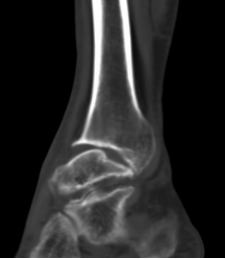

CT检查:提供高分辨率的骨结构影像,特别适用于评估关节内骨折和骨赘的形成情况;

MRI检查:更清楚、详细地显示软骨、滑膜组织的病变情况,它对早期软骨损伤及关节内软组织异常有较好的诊断价值,特别适用于复杂病例或需要进一步了解软骨状态的患者;